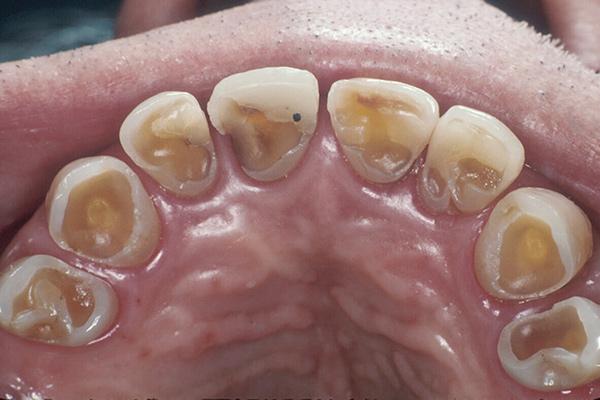

Sau khi quan sát, bác sĩ thấy rằng răng của Lý bị ảnh hưởng nghiêm trọng, ở những răng tương đối tốt có men mờ, một số răng bị lộ ngà vàng.

Lớp ngoài cùng của răng là men, bao bọc bên trong ngà răng. Ngà răng khi bị kích thích bởi sự lạnh, nóng, chua, ngọt... từ thức ăn, khi nhai sẽ có cảm giác đau đớn, cắn khó... Gọi chung là chứng ngà răng nhạy cảm.

Theo bác sĩ, cô Lý có thói quen nghiến răng khi ngủ, vì vậy bề mặt răng bị bào nhẵn. Khi cô ăn nhiều quả thanh mai, quả thanh mai thực hiện việc "khử khoáng", làm cho lớp men răng mỏng của cô Lý cuối cùng bị hỏng và lộ ra ngà răng.